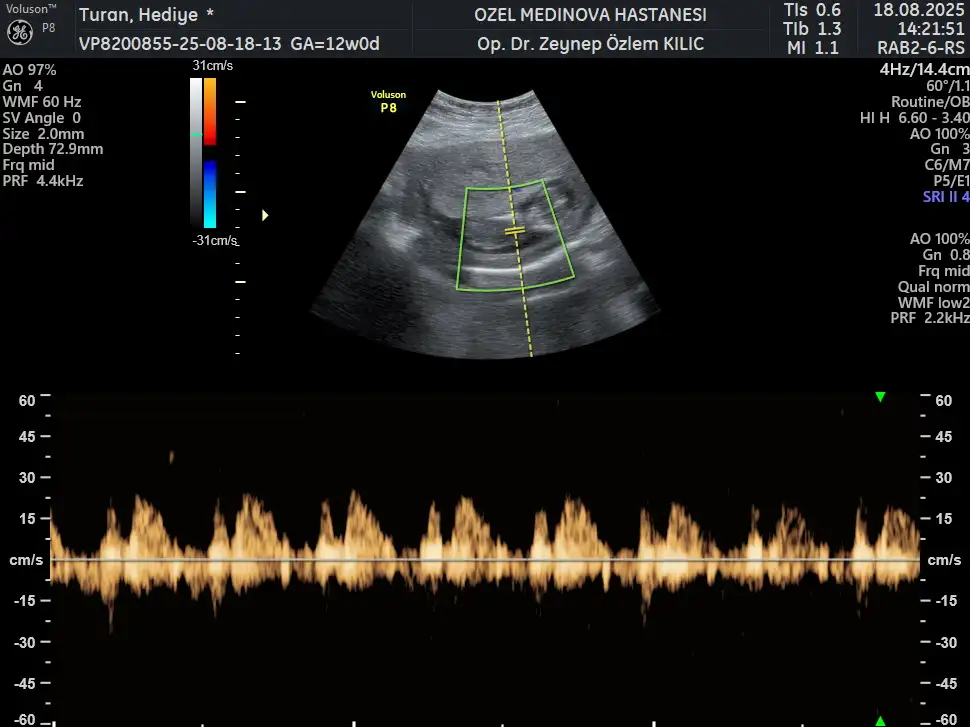

Erkek bencemerhaba 11+6 haftalık ilk ve son karından ultrason fotoğraflarını ekledim rica etsem bakabilir misiniz

Benim nedir sizce 12+1Erkek bence

MerhabalarBenim nedir sizce 12+1

13. haftadan sonraki bir ultrason fotoğrafı varsa chatgptye sorun bence nub teorisine göre benimkini ve arkadaşımın bebeğini doğru tahmin ettiBenim nedir sizce 12+1